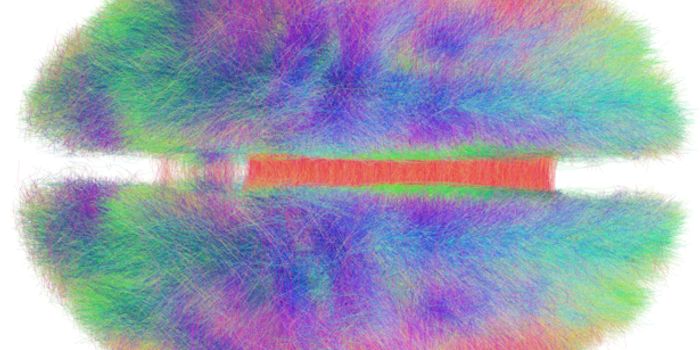

JUN 30, 2016NeuroscienceWhen there has been a traumatic brain injury (TBI) or there is a tumor or other problem in the brain, doctors need to kn ...